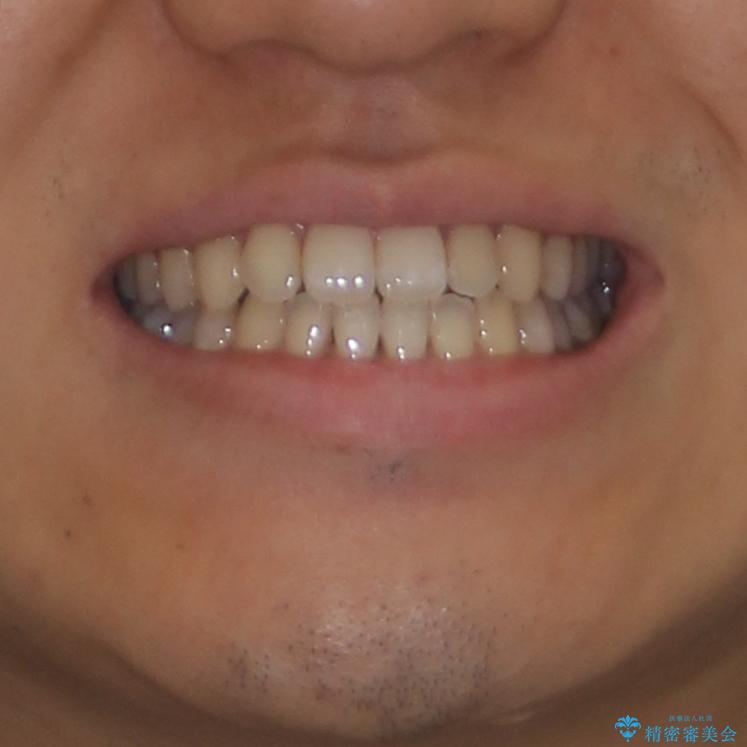

下顎前歯と上顎の部分矯正

- 患者様

- 30代男性

- 上下の前歯の叢生を気にして来院された患者様です。

前歯のみの矯正治療を希望でしたが、上顎臼歯が舌側転位していたため、上顎は全体を、下顎は前歯のみを矯正治療することとしました。